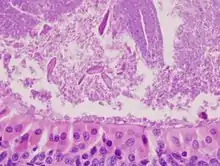

The appearance of this tumor under the microscope is unique. There are cystic spaces surrounded by two uniform rows of epithelial cells with centrally placed pyknotic nuclei. The cystic spaces have epithelium referred to as papillary infoldings that protrude into them. Additionally, the epithelium has lymphoid stroma with germinal center formation.